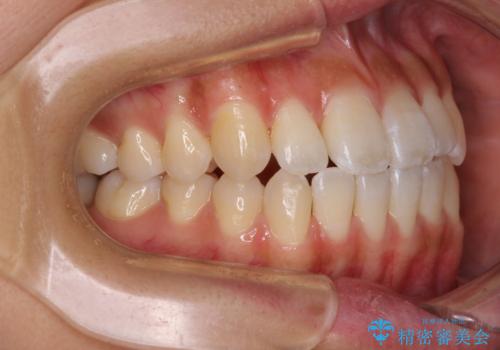

急速拡大装置で上顎骨を十分に拡大できたことで、非抜歯で八重歯を歯列に納めることができました。

患者様はもちろん、我々もここまで綺麗に仕上げられるとは想像もできず、お互いに大変満足な治療となりました。